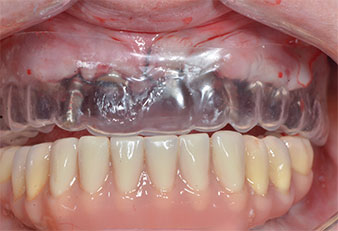

Trois ans après, le moment était venu pour elle de se doter d’une prothèse maxillaire du même type. Sur la base de la planification CBCT, l’élévation sinusale a été évitée grâce à la pose d'implants courts, et un gabarit chirurgical a été utilisé pour transférer les positions planifiées sur la crête alvéolaire (Figures 1 et 2).

Fig. 1 : Vue préopératoire de la crête maxillaire, où les positions implantaires ont été marquées à l'aide d’un gabarit chirurgical en plastique. Compte tenu de la faible hauteur de la crête, des implants postérieurs très courts sont planifiés.

Gabarit en plastique

Fig. 9 : Un gabarit en plastique révèle qu'il y a suffisamment de place pour que la prothèse existante serve de prothèse temporaire fixée sur les implants provisoires.